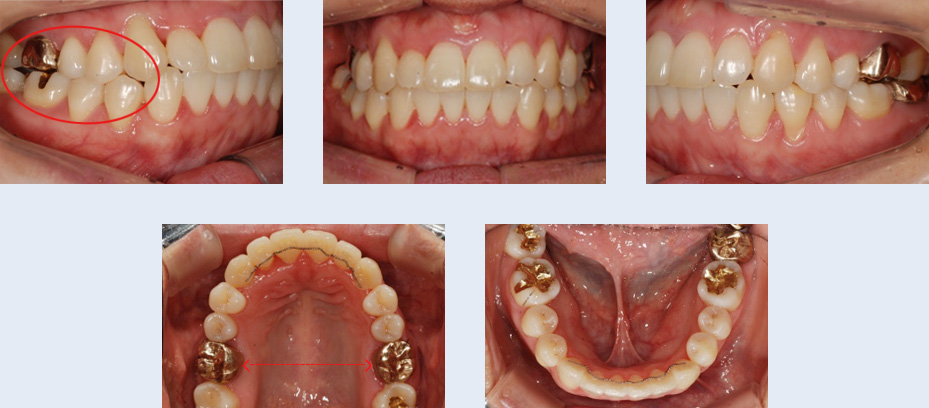

앞니 치열 불규칙하고 어금니가 잘 맞물리지 않아 소리가 나는 증상으로 내원한 22세 대학생입니다.

좌측 위 덧니가 관찰되었고 아래 어금니 배열이 바르지 않아 위 어금니와 정상적인 교합 관계를 보이지 않는

상태였습니다. 이를 빼지 않고 공간을 확보하기 위해 다음의 치료를 진행하였습니다.

앞니 치열이 고르게 개선 되었으며 어금니가 자연스럽게 맞물리는 정상교합이 되었습니다. 자연치아를 빼지 않고

약간의 치간 삭제를 통해 교정 치료가 완료되어 환자 분의 만족도가 높은 케이스였습니다.